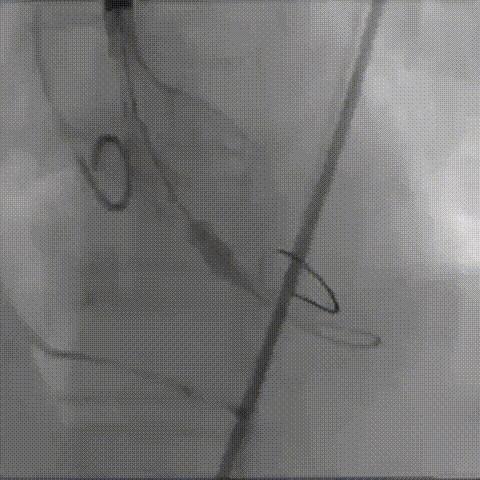

输送器顺利过弓、跨瓣

瓣膜标准位定位

瓣膜释放到工作位

工作位造影

位置理想,瓣膜完全释放

释放后造影